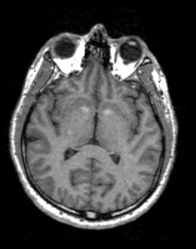

For the following example an image dataset of a human head was used.

After execution of the privacy module there is a additional surface visible on the front of the head surface.

This example shows the data in the 3D view in slicer before and after the usage of two different parameter settings in the module.